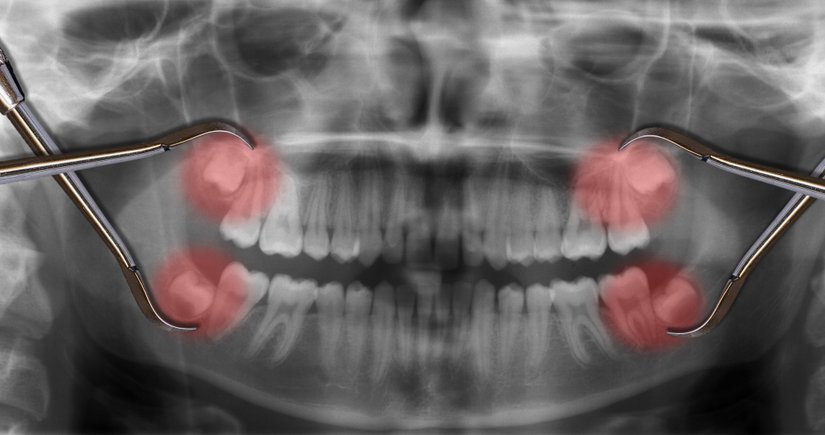

Yirmi yaş dişlerinin sıklıkla gömülü kalırlar, çıktıkları zaman doğru şekilde çıkmazlar ve diğer dişlere sürtünerek onların yapısını bozabilirler. Bu nedenle de ağrı ve enfeksiyona neden oldukları bilinmektedir. Bunun haricinde ise hiçbir işlevleri bulunmamaktadır. Dolayısıyla ağrıya neden oldukları zaman, diş hekimleri tarafından çekilerek hasta rahatlatılabilmektedir. 20 yaş dişleri çekilen kişilerin ağız fonksiyonlarında hiçbir azalma olmamaktadır. Aşağıda bu dişleri görmektesiniz: